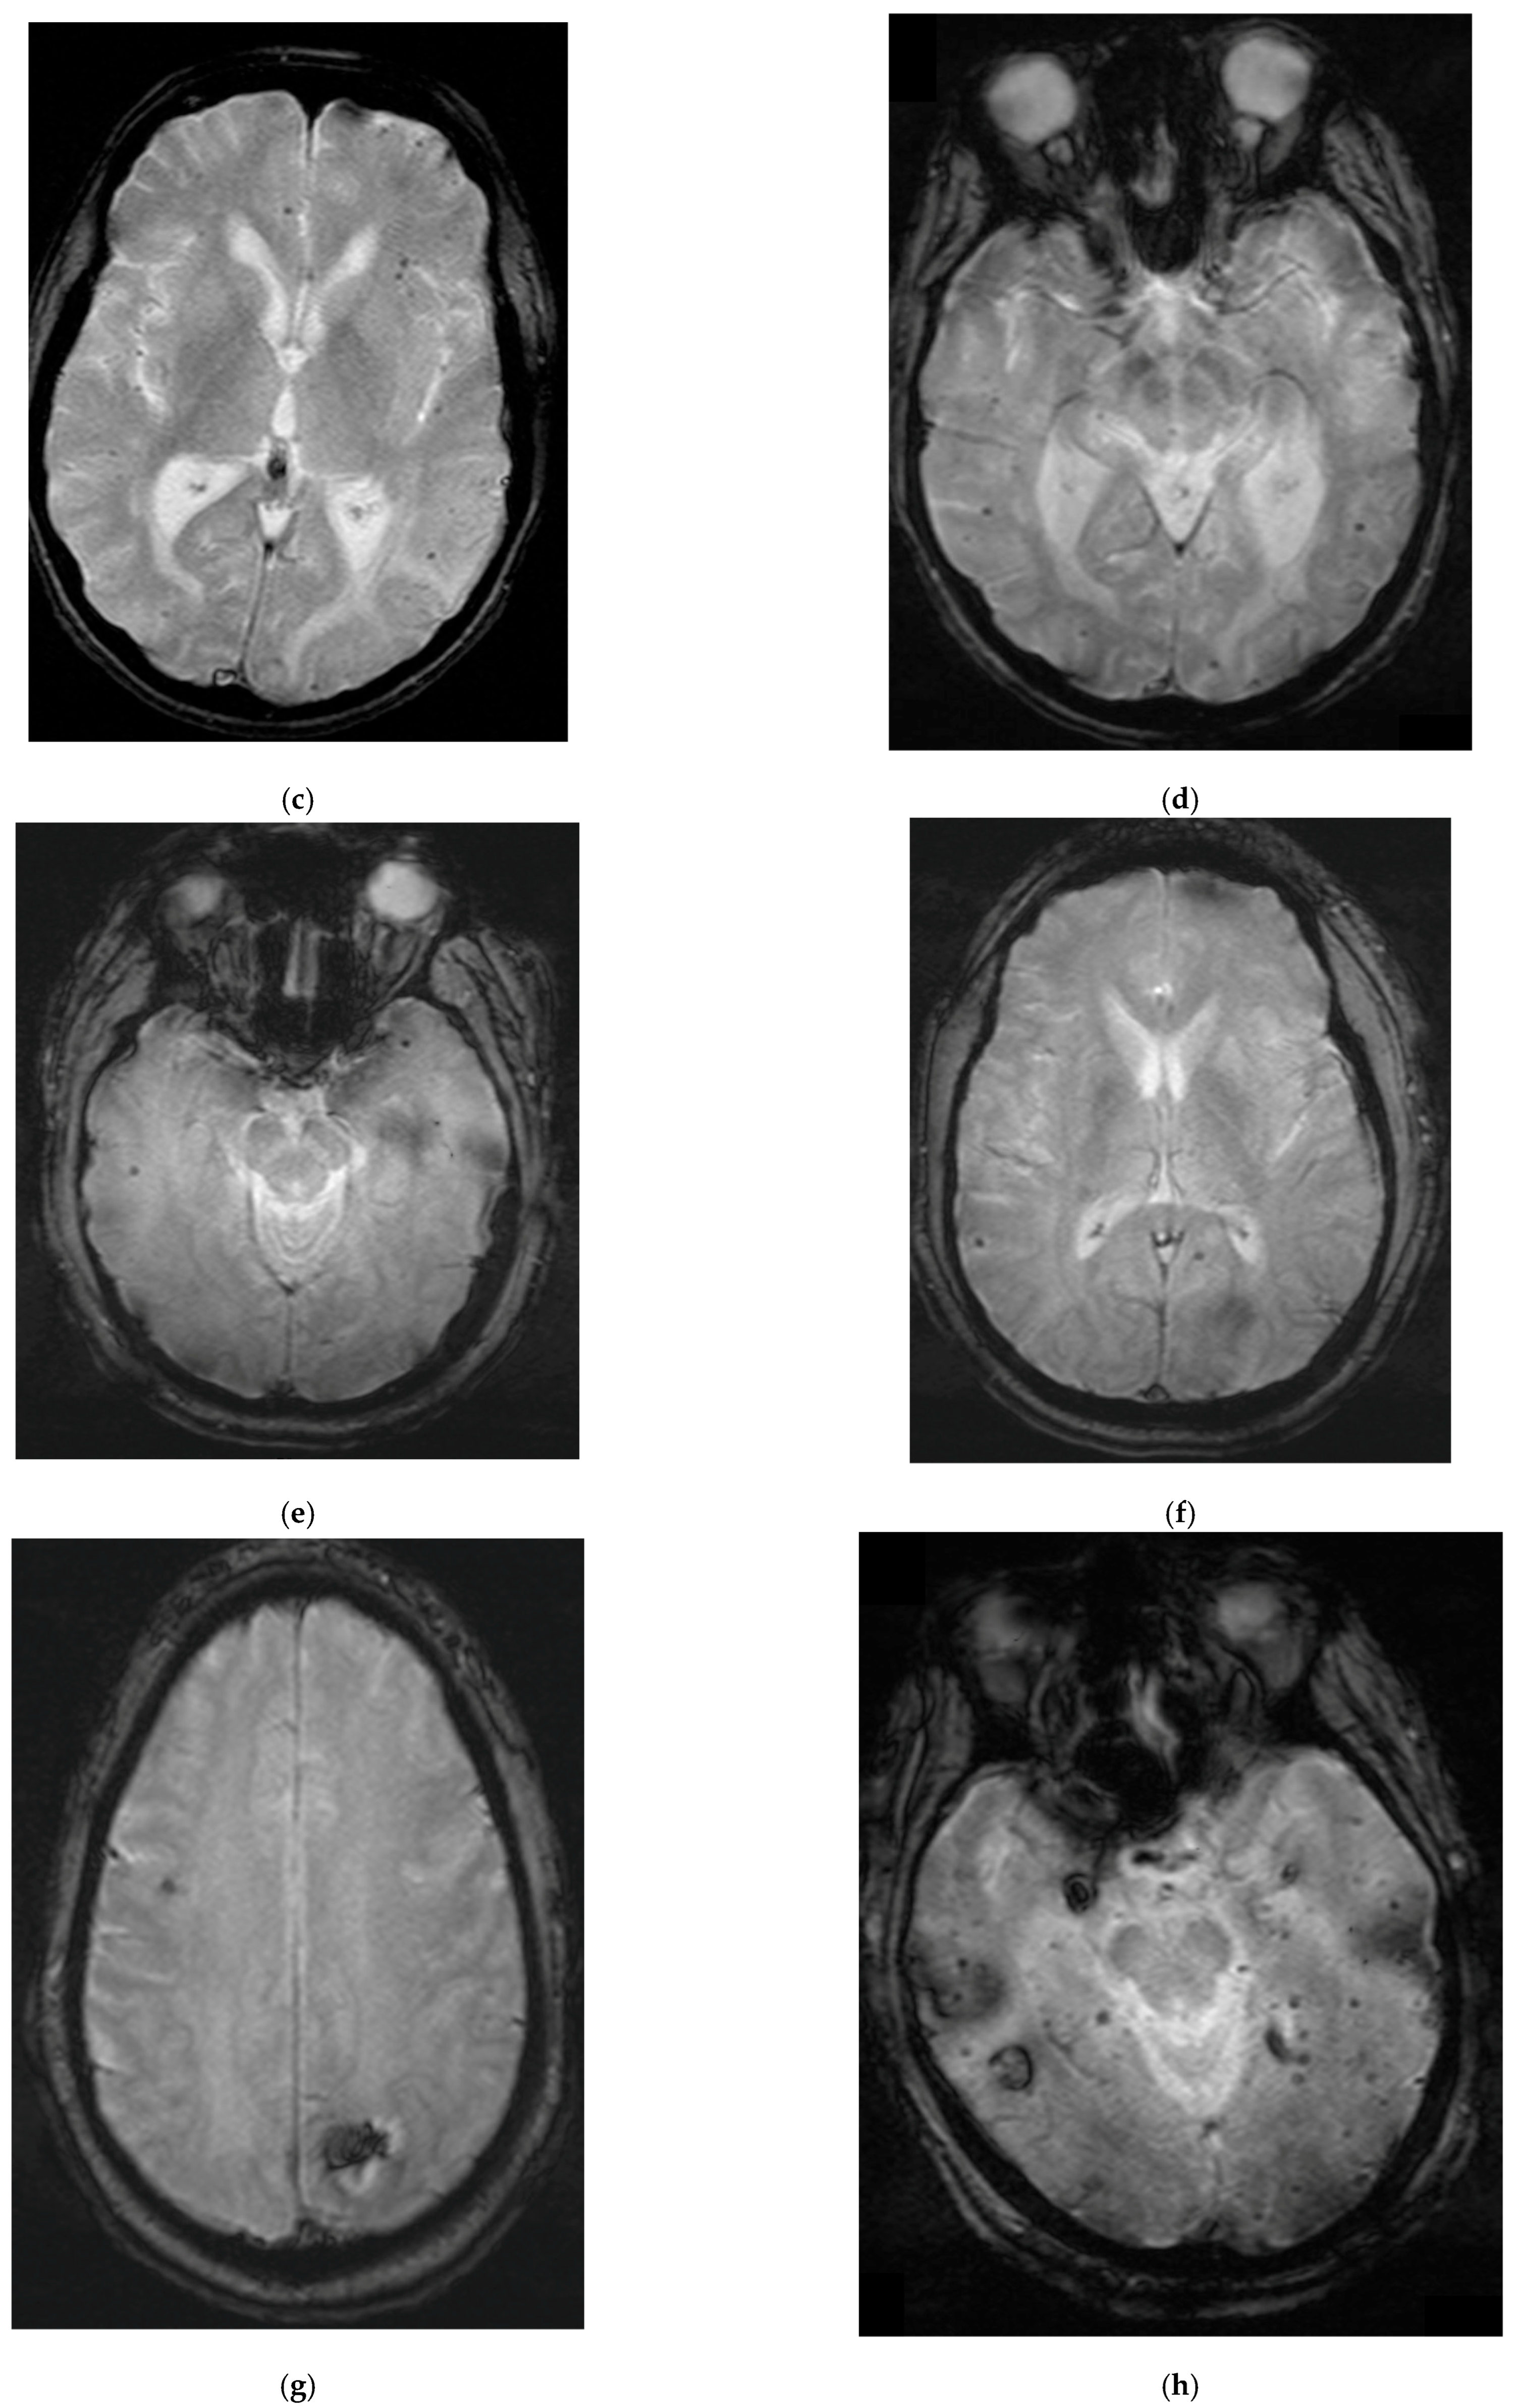

2. Case Summaries

2.1. Patient 1

2.2. Patient 2

2.3. Patient 3